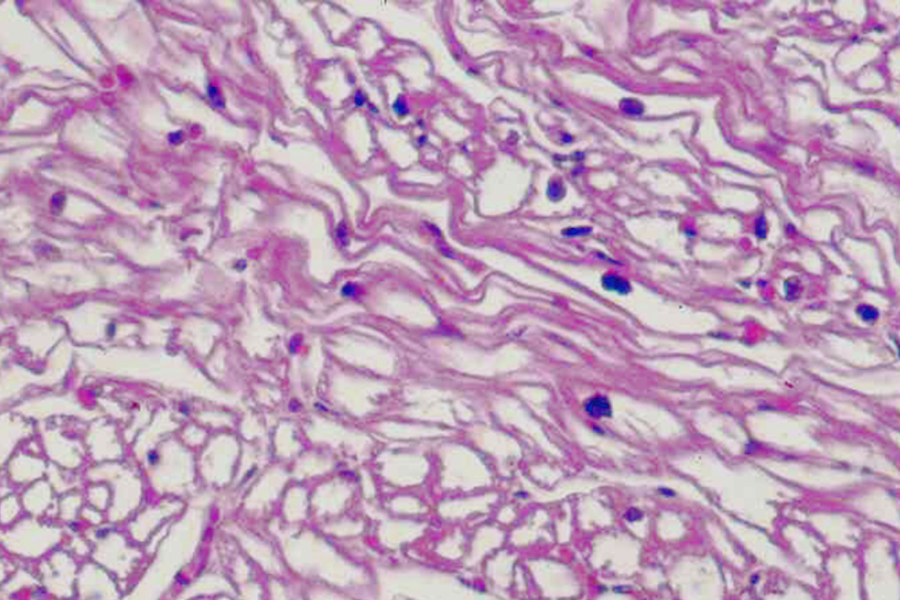

histologische Bilder

hypertrophe Kardiomyopathie

hypertrophe Kardiomyopathie

Pathology Residency and Fellowship Program, Brown University, Access 23. October 2022

Elliott P, McKenna WJ (2004) Lancet 363:1881-1891

Internet Pathology Laboratory , University of Utah, Access 23. October 2022

Thoracic Pathology, Cardiac Hemochromatosis, Access 23.October 2022